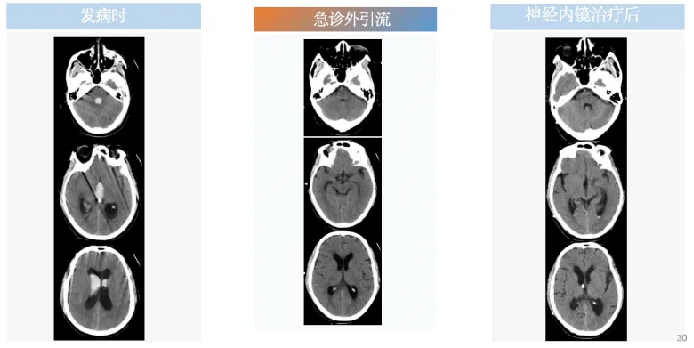

随后,医生紧急为老张实施双侧脑室外引流术,血肿逐渐减少,家属总算松下一口气。但接下来数天的治疗多次尝试拔除引流管均未成功,随着病情的加剧,患者的意识逐渐模糊,颅内感染的风险在增加。在这个关键时刻,航空总医院及时启动多学科专家联合会诊机制,神经外四科主任肖庆给出针对性治疗方案。

经过充分准备,肖庆为患者行神经内镜检查术+脑脓肿清除术+脑室腹壁长程引流术+脑脊液置换术+气管切开术。术中清除多处陈旧积血块及絮状物炎性改变;术后持续引流,复查头颅CT检查脑室内积血消失,脑室扩张形态减轻,脑水肿缓解;同时,纠正低蛋白血症、肝功能异常,加强肺部感染治疗,抗炎改善脓毒血症,纠正炎性指标,肠内外营养纠正营养不良,纠正电解质紊乱……